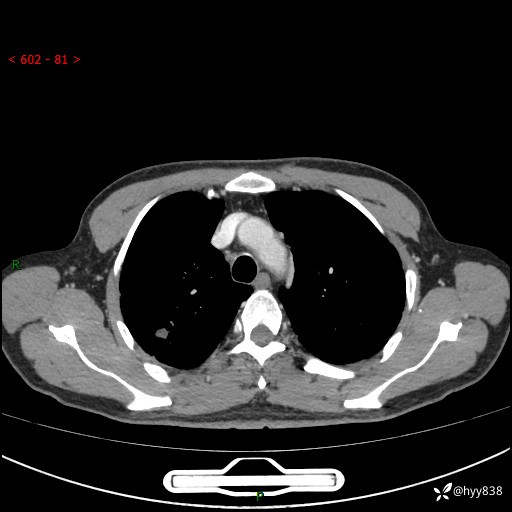

69岁/男,发现肺部病变6天。该有的征象都有,肉芽肿 VS 肿瘤,一念之间---(有结果)

主诉:发现肺部病变6天。

现病史:患者6天前于我院泌尿外科住院,住院期间行胸部CT检查,提示“肺部病变”,患者无畏寒、发热、盗汗、咳嗽、咳痰、咯血、胸痛、呼吸困难,无反酸、腹痛、腹泻、头痛、头晕等不适。未予特殊处理,现为进一步诊治,门诊以“肺肿物”收入我科。 患者本次起病以来,精神食欲尚可,大小便正常,体力及体重无明显变化。

胸部CT平扫+增强